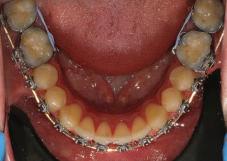

20 Dental Tribune Bulgarian Edition / октомври 2022 г. П ациентите със завършен растеж и скелетни проблеми обикновено представляват предизвикателство за ортодонт ската практика. Необходимостта от изваждане на зъби в комбинация с особеностите на възрастовата ортодонтия изисква особено внима ние. Фокусът върху критично важното значение на позицията на долните резци във връзка с дългосроч ната стабилност и постигането на оптимални оклузални взаимоотношения при затварянето на екстракционните пространства лесно може да излезе извън контрол. Когато към тези чисто кли нични проблеми се добави и стресът от натоваре ната практика, предизвикателството става още по-голямо. Всички тези фактори налагат използ ването на доказан подход с ясни и последовател ни стъпки, в което се разкрива силата на дисциплината „Алекзандър“ – предвидим протокол през целия процес на елиминиране на ротациите, ниве лиране на дъгите, затваряне на екстракционните пространства и финализиране на случая. Именно такъв е и случаят, който презентираме –екстракционен, скелетен клас 3 при възрастен па циент, лекуван по системата „Алекзандър“. ПРЕДВИДИМИ РЕЗУЛТАТИ ПРИ ПАЦИЕНТИ СЪС ЗАВЪРШЕН РАСТЕЖ И СКЕЛЕТЕН КЛАС 3, ИЗПОЛЗВАЙКИ ЕКСТРАКЦИОННО ЛЕЧЕНИЕ ПО ДИСЦИПЛИНАТА „АЛЕКЗАНДЪР“ Д-р Радой Димитров, България Преди започване на лечение клиничен случай | ортодонтия Фиг. 1а–1e Преди започване на лечение. Пациентът пристига в практиката с основното оплакване от невъзмож ност за нормално дъвчене. Снета е цялата необходима диагностична ин формация. Фиг. 1f–1h Снимки в профил и анфас. Фиг. 1i–1k Панорамна снимка, телерентгенография и анализ на телерент генография. Фиг. 1а Фиг. 1d Фиг. 1f Фиг. 1g Фиг. 1h Фиг. 1e Фиг. 1b Фиг. 1c Фиг. 1i Фиг. 1j Фиг. 1k

closed.

21Dental Tribune Bulgarian Edition / октомври 2022 г. ДИАГНОСТИЧНИ РЕЗУЛТАТИ: 1. Възраст на пациента: 21 години 2. Скелетен клас III (ANB 0) 3. Зъбен клас 3 4. Ръбцова захапка във фронта, кръстосана в дисталните участъци 5. Тясна горна челюст 6. Overjet – 0 мм, Overbite – 0 мм 7. Несъответствие на горната с долната средна линия 8. Единични контакти в ЦО 9. Хиподивергентен тип на растеж SN/MP – 33.5 10. Неравен гингивален контур 11. Неравна линия на усмивката 12. Тенденция за рецесии в долен фронт ПРЕПОРЪЧИТЕЛНО ЛЕЧЕНИЕ: Пълно ортодонтско лечение с метални брекети „Алекзандър“ Корекция на клас 3 захапката в областта на кучешките зъби с екстракция на първите пре молари в долна челюст Корекция на кръстосаната захапка в дистални участъци Коригиране на ръбцовата захапка във фронта Подобряване на ОJ и OB на пациента Стрипинг в долен фронт Подреждане на зъбите в горната и долната челюст Професионално хигиенизиране и профилактични дентални прегледи са препоръчителни на всеки 6 месеца. 1-ви месец След 1 месец са залепени брекети в горната челюст – поставена е еластична дъга. 016 NiTi. В долната челюст са елиминирани ротациите, поставена е стоманена дъга. 016SS, закалена с ток, и еластична верижка за затваряне на пространствата. 3-ти месец В долната челюст е поставена трета дъга – 17 x 25 NiTi с къси лигатури и верижка

В горната челюст се затварят пространствата с дъга .016SS и верижка. 5-и месец На 5-ия месец след залепяне на брекетите в долната челюст е поставена стоманена дъга 16 x 22 SS с четвъртито сечение, омега луп и тай бек. В горната челюст е поставена дъга 17 x 25 NiTi. Поради липсата на стабилни оклузални контакти са поставени лингвални верижки в областта на моларите, за да се предотврати нежелана ротация на 7-ите зъби. 6-и месец На 6-ия месец от началото на лечението са екстрахирани долните първи премолари, поставена е дъга 16 x 22 SS със затваряща чупка teardrop. Чупката се активира всеки месец по 1 мм с чинч-бек. клиничен случай | ортодонтия СТЪПКИ НА ЛЕЧЕНИЕТО Начало на лечението Лечението започва с поставяне на апарат за бърза експанзия в горната челюст. През първия месец от лечението са направени 24 оборота на апарата за експанзия. Залепени са брекети в долната челюст, поставена е дъга 17x25 CuNiTi, като са предпи сани клас 3 ластици (1/4”,4 1/2 oz) по време на сън, за да се осигури контрол върху торка на долните резци. Фиг. 2а Фиг. 3a Фиг. 4a Фиг. 3b Фиг. 4b Фиг. 3c Фиг. 4c Фиг. 3d Фиг. 4d Фиг. 3e Фиг. 4e Фиг. 5a Фиг. 5b Фиг. 5c Фиг. 5d Фиг. 5e Фиг. 6a Фиг. 6b Фиг. 6c Фиг. 6d Фиг. 6e Фиг. 7a Фиг. 7b Фиг. 7c Фиг. 7d Фиг. 7e Фиг. 2b Фиг. 2c Фиг. 2d